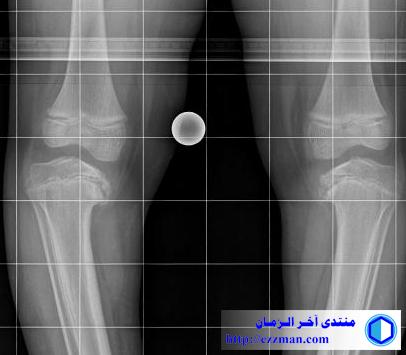

لاحظ انحراف على مستوى مفصل الركبة وهذا يسبب ألام عند المريض

المسيح الدجال أفحجوقد يكون هذا التشوه بسبب مرض بلاونت (Blount's disease)